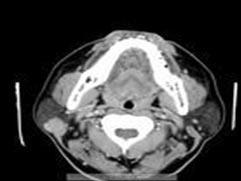

原发性腮腺淋巴瘤

腮腺部位出现的无痛性肿块,手术活检、病理组织检查确诊。80%的病人在诊断时为Ⅰ、Ⅱ期。原发性淋巴采用AnnArbor分期。但该病的误诊率较高,原因是就诊时常常怀疑其他恶性肿,而很少想到该病。